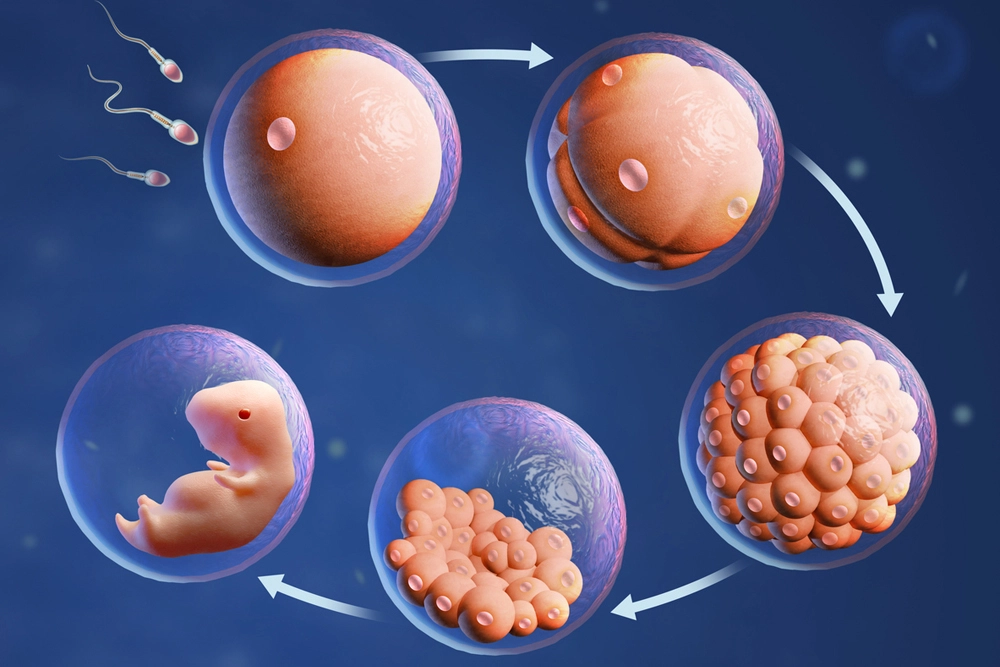

In vitro fertilization is a medical technique in which a woman’s eggs are retrieved from her ovaries, fertilised with sperm in an external lab dish, the resulting embryos are cultured for 3-5 days and then one or more healthy embryos are transferred into the uterus to achieve pregnancy. Intracytoplasmic sperm injection (ICSI) is a specialised form of IVF treatment. It involves injecting live sperm into an egg through an artificial process. After fertilization, it forms an embryo. ICSI is most frequently used by medical professionals when a patient’s ability to conceive is impacted by male infertility.

In vitro fertilization (IVF) is a type of fertility treatment that fuses sperm and eggs to form an embryo through scientific methods. This procedure of handling eggs and sperm to achieve pregnancy is known as Assisted Reproductive Technology (ART).

During IVF, the eggs and sperm of the couple or gametes from a donor are used to create embryos. Embryos are then implanted in the uterus of a female partner or surrogate (if medically indicated).

Embryo Culture

After egg retrieval, the eggs are fertilised with sperm in the laboratory.

- The healthiest sperm are selected

- Fertilisation takes place in a controlled environment

- The resulting embryos are carefully monitored for 3–5 days

Only healthy, well-developed embryos are chosen for transfer.

Embryo Transfer

In this final step, the selected embryo is gently placed into the uterus.

- This is a simple and painless procedure

- No anaesthesia is usually required

- The embryo is placed at the ideal location to support implantation

After the transfer, a pregnancy test is done approximately two weeks later to confirm the result.

IVF is a step-by-step process that combines medical expertise with advanced laboratory care to maximise the chances of a healthy pregnancy. With proper guidance and personalised treatment, you can successfully achieve your dream of parenthood.